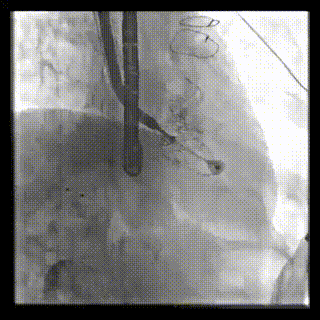

本周三例接受LuX-Valve Plus經血管三尖瓣置換術的患者中,第一例患者為冠狀動脈旁路移植術+Bentall+二尖瓣成形術后;第二例患者為永久起搏器植入術后,存在跨三尖瓣導線;第三例患者合并房顫、房缺及左心耳封堵術后。

三例患者入院后,葛均波院士團隊周達新教授、潘文志教授、張源博士、陳莎莎博士及心超室的潘翠珍教授、李偉教授對患者的情況進行詳細評估和討論,最終決定為三例患者選擇LuX-Valve Plus40mm、50mm和50mm型號的瓣膜進行手術治療。手術后即刻拔除氣管插管,術后患者三尖瓣反流癥狀得到顯著改善,復查心超結果顯示人工三尖瓣瓣膜支架固定穩定,瓣葉關閉形態未見異常,未見明顯反流。